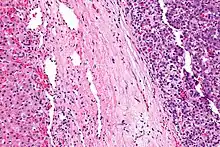

| Micrograph of a hepatoblastoma. H&E stain. | |